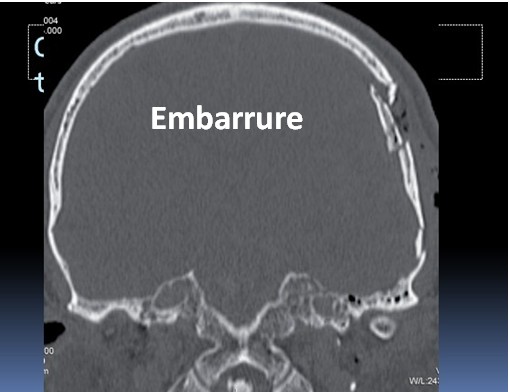

Types : fracture linéaire, fracture embarrée, fracture de la base du crâne

Les indications principales sont [9] : hématome extradural >30 ml, hématome sous-dural avec déplacement de la ligne médiane, contusion cérébrale expansive, fracture embarrée compressive.